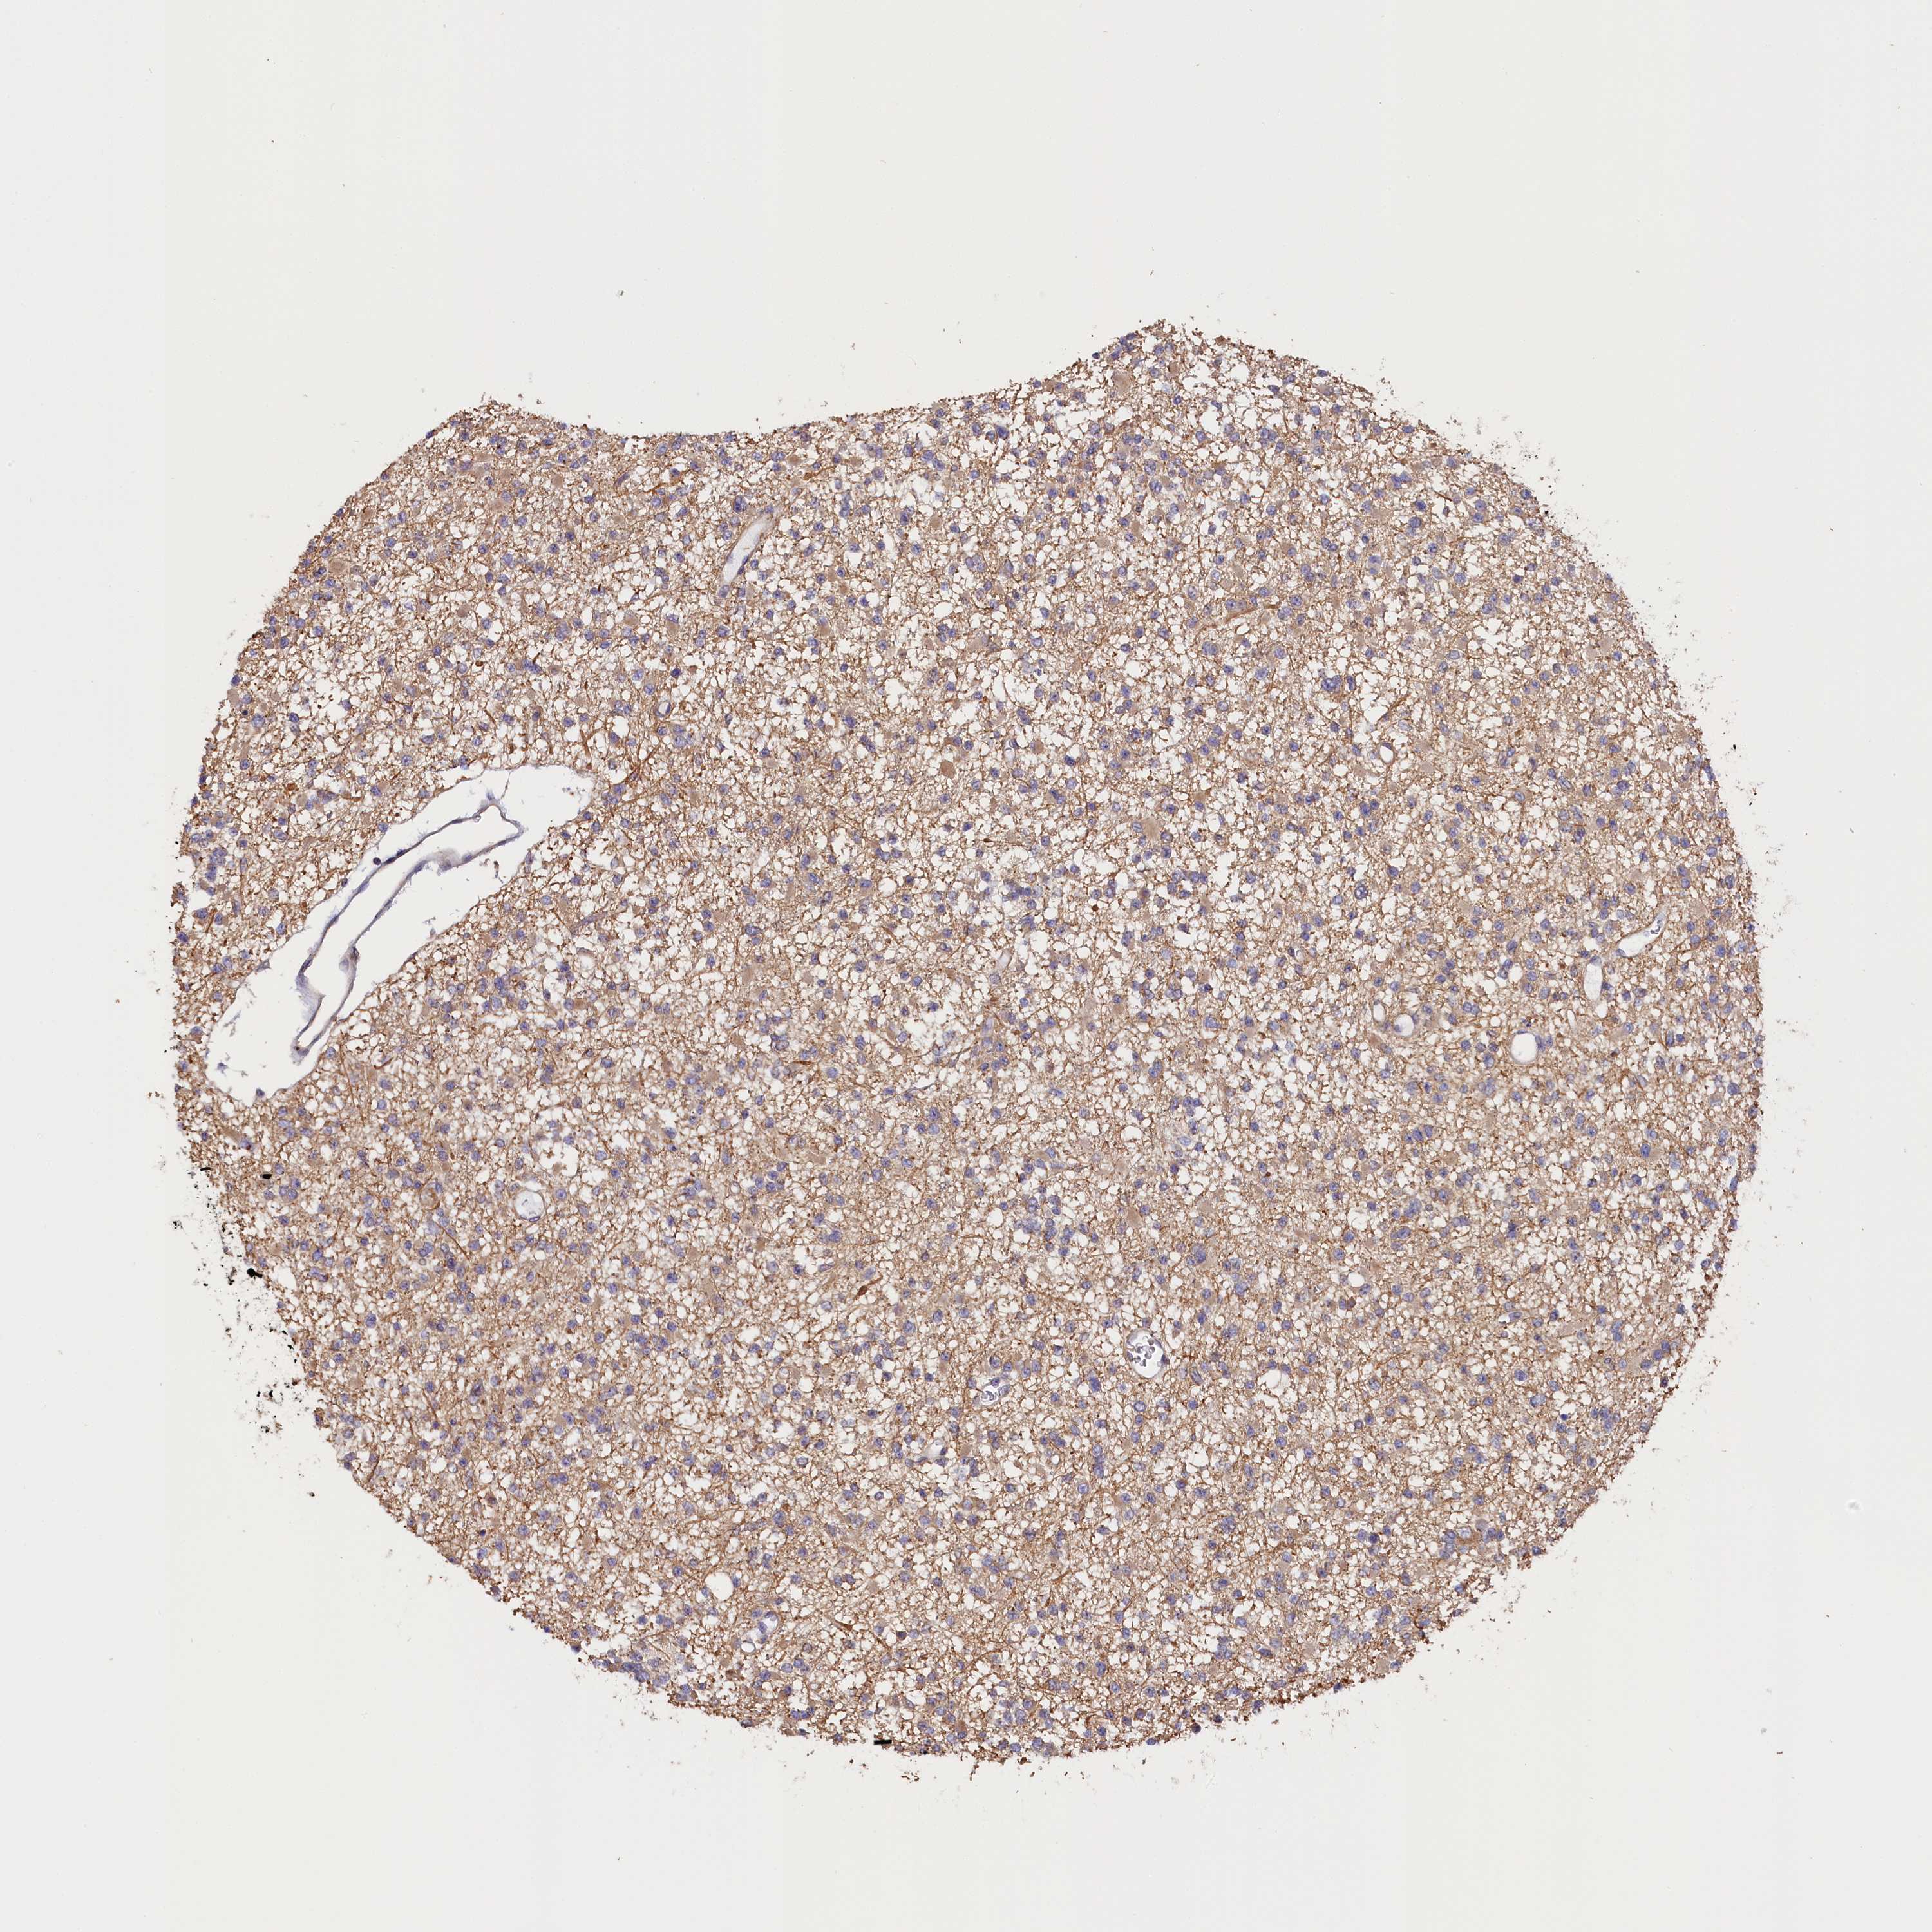

GLIOMA - Protein expressioni

A mouse-over function shows sample information and annotation data. Click on an image to view it in a full screen mode. Samples can be filtered based on level of antibody staining by selecting one or several of the following categories: high, medium, low and not detected. The assay and annotation is described here.

Note that samples used for immunohistochemistry by the Human Protein Atlas do not correspond to samples in the TCGA dataset.

Antibody stainingi

Antibody staining in the annotated cell types in the current human tissue is reported as not detected, low, medium, or high, based on conventional immunohistochemistry profiling in selected tissues. This score is based on the combination of the staining intensity and fraction of stained cells.

Each image is clickable and will lead to virtual microscopy that enables deeper exploration of all samples and also displays staining intensity scores, fraction scores and subcellular localization as well as patient and tissue information for each sample.

Antibody HPA041165

Antibody HPA041839

Staining

High

Medium

Low

Not detected

Intensity

Strong

Moderate

Weak

Negative

Quantity

>75%

75%-25%

<25%

None

Location

Nuclear

Cytoplasmic/membranous

Cytoplasmic/membranous,nuclear

Glioma, malignant, High grade

Glioma, malignant, Low grade